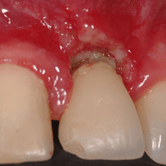

Fístula gingival

Una fístula gingival es un canal anormal que se forma en las encías y drena pus debido a una infección.

Los pacientes notan una pequeña abertura en la encía que supura pus.

Esto indica una infección crónica que necesita tratamiento. El tratamiento puede incluir la limpieza del área infectada y el uso de antibióticos.